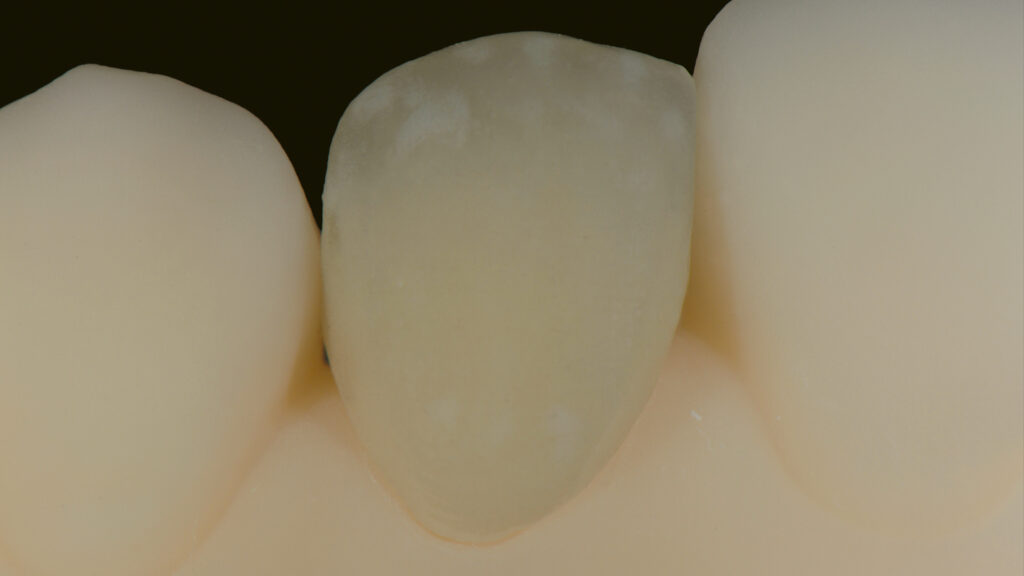

Emergenzprofil und Gestaltung des Kronenrandes

Die Gestaltung des marginalen Randes („Präparationsrand”) im bukkalen Bereich erfolgt in Absprache mit dem Zahnarzt ca. 0,2 mm subgingival (Abb. 52). Palatinal endet die Verblendkeramik supragingival, um hier die biologischen Vorteile des Zirkonoxids zu nutzen (Weichgewebekonditionierung) (Abb. 53). Vor allem im Frontzahnbereich wird das individualisierte Emergenzprofil als wichtiger Faktor für die Rekonstruktion einer zufriedenstellenden Ästhetik angesehen. Zudem werden im Frontzahnbereich mit Zirkonoxid biologisch und ästhetisch bessere Ergebnisse erzielt als mit Titan, das bei dünnem Gingiva-Biotyp durchscheinen kann (Abb. 54 und 55).

Die individuelle Formgebung der ASC-Implantatkronen ermöglicht einen reizfreien Schleimhautkontakt mit Titanadapter und konischer Innenverbindung zum Implantat (Abb. 56 und 57). Die keramische Verblendung des Zirkonoxid-Abutments erfolgt analog und ebenso detailgetreu wie beim keramischen Veneer und mit der gleichen Verblendkeramik (Lumex AC). Nach der Verblendung wird die Implantatkrone auf dem Meistermodell verschraubt und eine letzte Kontrolle der Kontaktflächen (Abb. 58 und 59), der Artikulation, der seitlichen Bewegungen und der Eckzahnführung durchgeführt. Abbildung 60 zeigt den nahtlosen Übergang der Implantatkrone zur natürlichen Gingiva. Eine Überkonturierung könnte zu einer apikalen Verschiebung führen. Eine polar_eyes-Aufnahme macht das Innere der Krone und die Details besser sichtbar (Abb. 61).